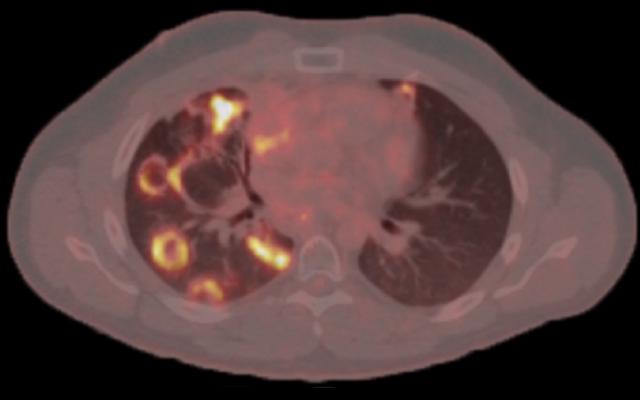

Samenvatting Lees volledig artikel Artikelinformatie Online verschenen op 25 februari 1923 Citeer dit artikel als Ned Tijdschr Geneeskd. 1923;67:862-6 Heb je nog vragen na het lezen van dit artikel? Check onze AI-tool en verbaas je over de antwoorden. ASK NTVG Ook interessant Beeldquiz Ringvormige afwijkingen op een longscan Diagnose in beeld Ringvormige afwijkingen op een longscan Beeldquiz Een man met een ringvormige vlek Meer gerelateerd … Reacties Login om een reactie te plaatsen